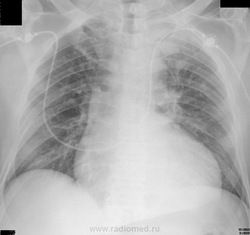

Эхо - хорошо, да и тут кое-что по КТ видно. Минусом бронхоэктазы и пневмоторакс, плюсом невыраженный застой и достаточно значимое расширение камер сердца слева (справа тоже несколько увеличены, но не столь выраженно).

С сердцем поторопился: уже и сам увидел – увеличение левых камер сердца есть.

Но есть и значительное уменьшение объёма нижней доли левого лёгкого, причём не только от сдавления его выпотом (смотрим междолевую плевру). Ещё мне кажется, тут есть ателектаз S10 и, возможно, частичное спадение S6, S9. Или же медиастинальный выпот симулирует всё это? Я вижу разницу в плотности ЭТОЙ структуры с плотностью паракостального экссудата. Но тогда чем объяснить уменьшение объёма нижней доли?

через 12 дней. Ваше слово, уважаемые коллеги! NIKOLAS

Лизирование кровоизлияния, хорошая динамика.

Явная положительная динамика.